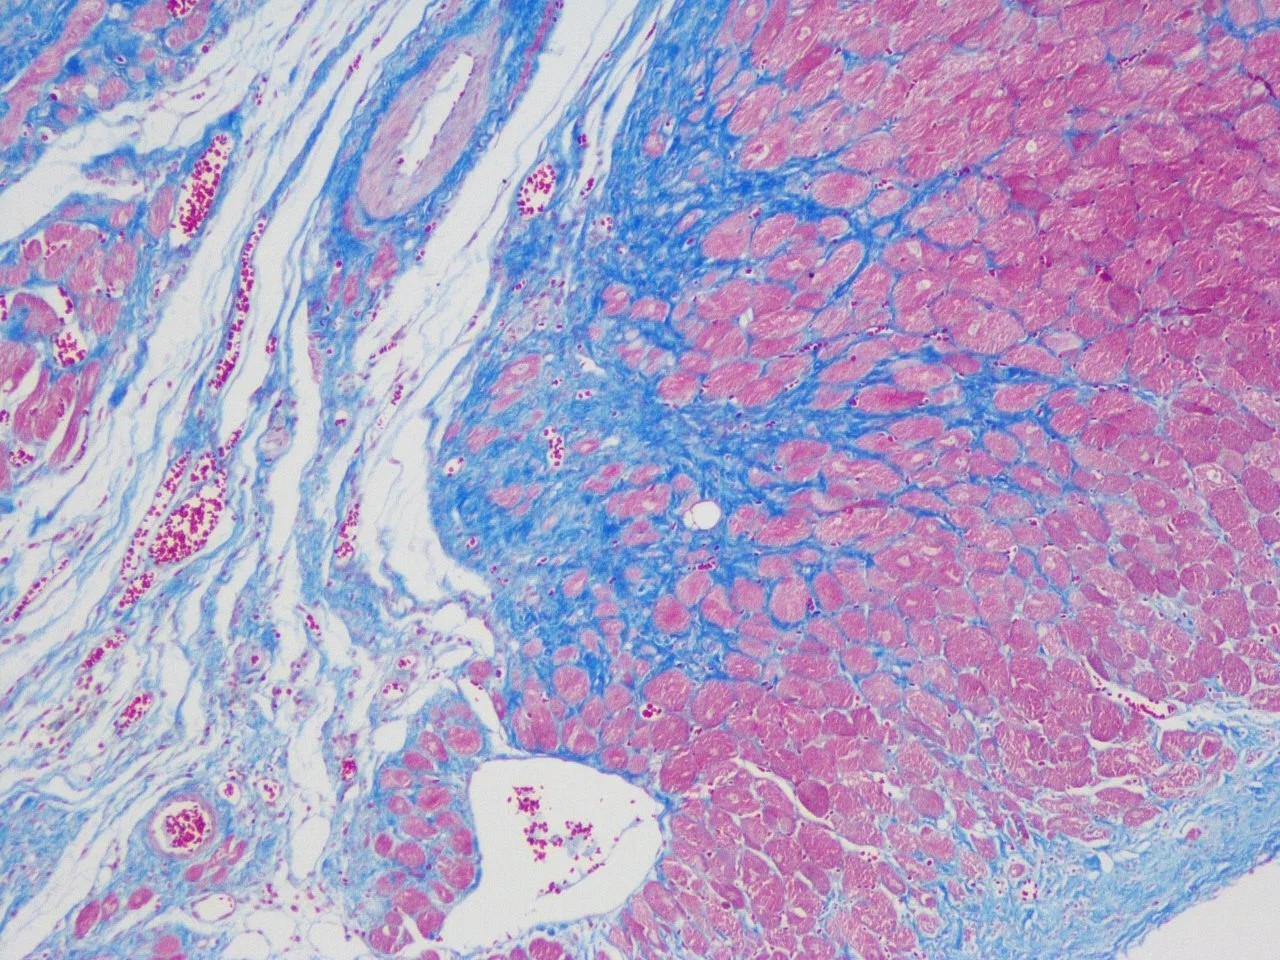

Masson’s三色染色法(Masson’s Trichrome Stain),是最常被使用的染色法之一,又稱Masson’s染色 (Masson 膠原纖維三色染色液),是比較經典的膠原纖維染色法(collagen fiber staining method)。該方法利用結締組織(connective tissues)中陰離子生物染料(anionic biological dyes)和分子量(molecular weights)的不同滲透性。分子量小的染料很容易穿透結構緻密、滲透性低的組織,而分子量大的染料只能進入結構疏鬆、滲透性好的組織,因此不同的組織成分呈現出不同的顏色。傳統的膠原纖維 Collagen fiber染色技術,主要用於膠原纖維與肌肉纖維的鑑別染色,尤其經常被用以觀察組織的纖維化(fibrosis)。故常被用於腎臟、肺臟與肝臟等組織的纖維化判定依據與投藥改善的評估方式之一。

本品為試劑盒,主要成分如下:A液為2.5%重鉻酸鉀(2.5% Potassium dichromate),B液、C液等體積混合為魏格鐵蘇木精染液(Weigert iron hematoxylin dye solution),D液為麗春紅酸品紅(Ponceau acid fuchsin),E液為1 %磷鉬酸溶液(phosphomolybdic acid solution),F液為2.5%苯胺藍溶液(2.5% aniline blue solution)。結締組織切片(connective tissue sections stain)經Masson’s三色染色液染色後,膠原纖維(collagen fibers)呈天藍色至亮深藍色,肌纖維(muscle fibers)、細胞質(cytoplasm)、纖維素(cellulose)、角質白(keratinous white)呈紅色至紫紅色,紅血球細胞(red blood cells)呈淡紅色。